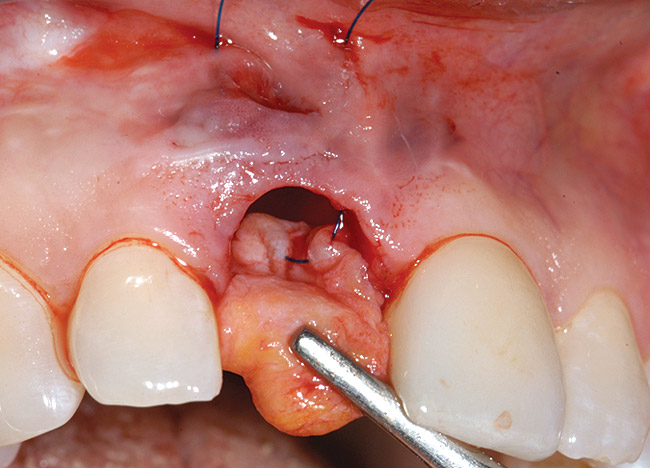

A 39-year-old woman presented with a failing endodontically treated maxillary right central incisor. Clinical and radiographic examination revealed a thick, flat periodontal biotype, high smile line, and a fistulous tract of the labial vestibule opposite the incisor (Figure 16 and Figure 17). Also noted post-extraction was a thin (< 2 mm) labial plate with 8 mm of vertical bone loss (Figure 18). Treatment consisted of a conservative flapless extraction with placement of a free connective tissue graft (Figure 19) sutured through the socket, along with placement of a bone mineralized allograft (MinerOss) (Figure 20 and Figure 21). Five months post-extraction, a root-form implant was placed, nonsubmerged, along with a bovine bone xenograft as a veneer into a sub-periosteal labial pouch (Figure 22 through Figure 24). A provisional crown was placed 3 months later, allowing for adequate soft-tissue grooming (Figure 25).

Figure 18  Post-extraction socket defect with loss of labial plate.

Figure 18

Figure 19  Connective tissue graft introduced via extraction socket.

Figure 19